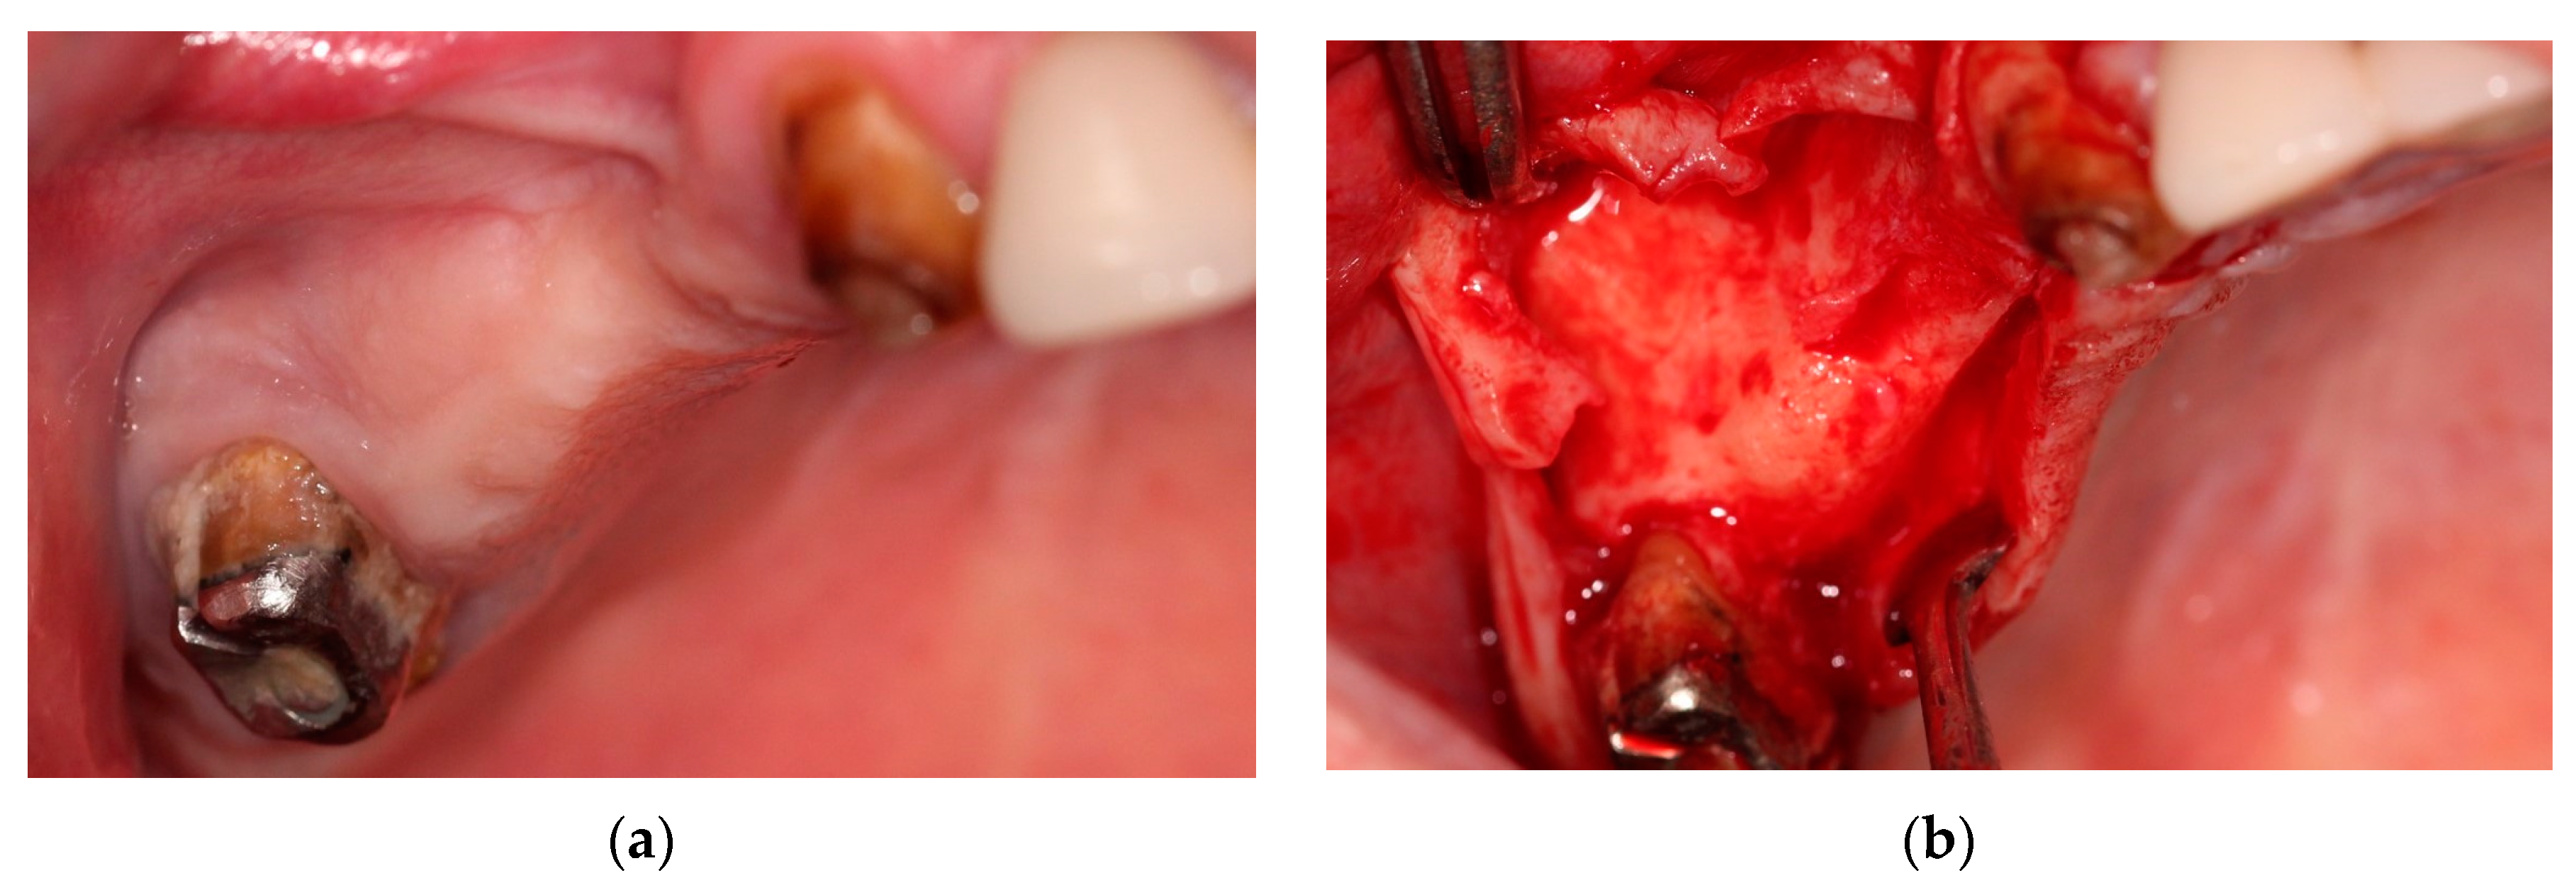

2. Case Presentation

2.1. Clinical History

2.3. Surgical Technique

2.3.1. Preoperative Preparation

2.3.2. Surgical Steps